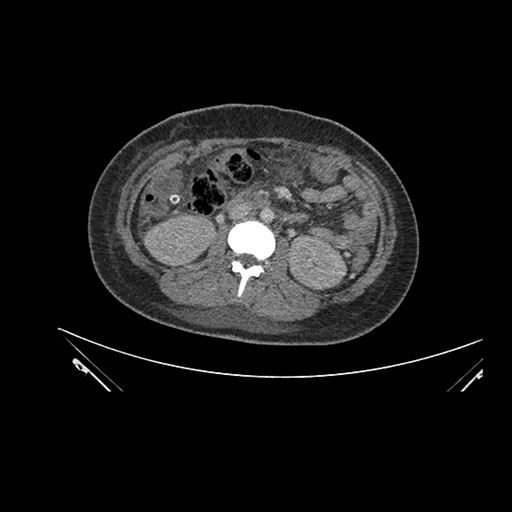

Axial Arterial

Axial Venous